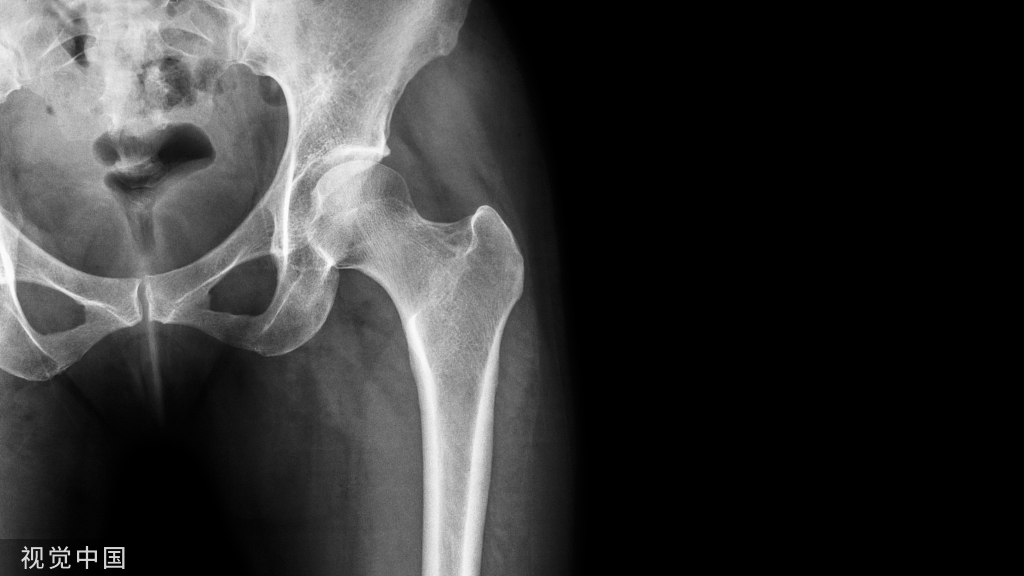

跟骨骨折为临床常见病,发病率高,占跗骨骨折的60%,全身骨折的2%。 跟骨骨折治疗困难,预后差。 治疗方案个体化强,方法多种多样。 跟骨骨折后,形态发生复杂的变化,包括G角、B角、宽度、高度、后关节面的对合情况等等。

跟骨的解剖学标志,最重要的就是两个角度

Bohler’s角:缩小、消失或反角,反映后关节面的塌陷Gissan‘s角:反映跟距关节内骨折的严重程度